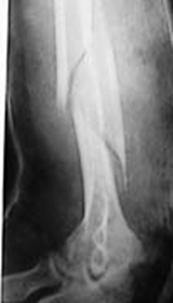

Fracturi simple: SPIRALA OBLICA TRANSVERSALA

Fractura spirala de Fractura transversa de diafiza femurala Fractura spirala de diafiza tibiala

diafiza humerala

Fractura spirala de diafiza tibiala Fractura oblica de diafiza tibiala Fractura transversala de diafiza tibiala

Fracturi cominutive

Fracturi spirala cominutive de Fractura complexa de diafiza radiala diafiza humerala